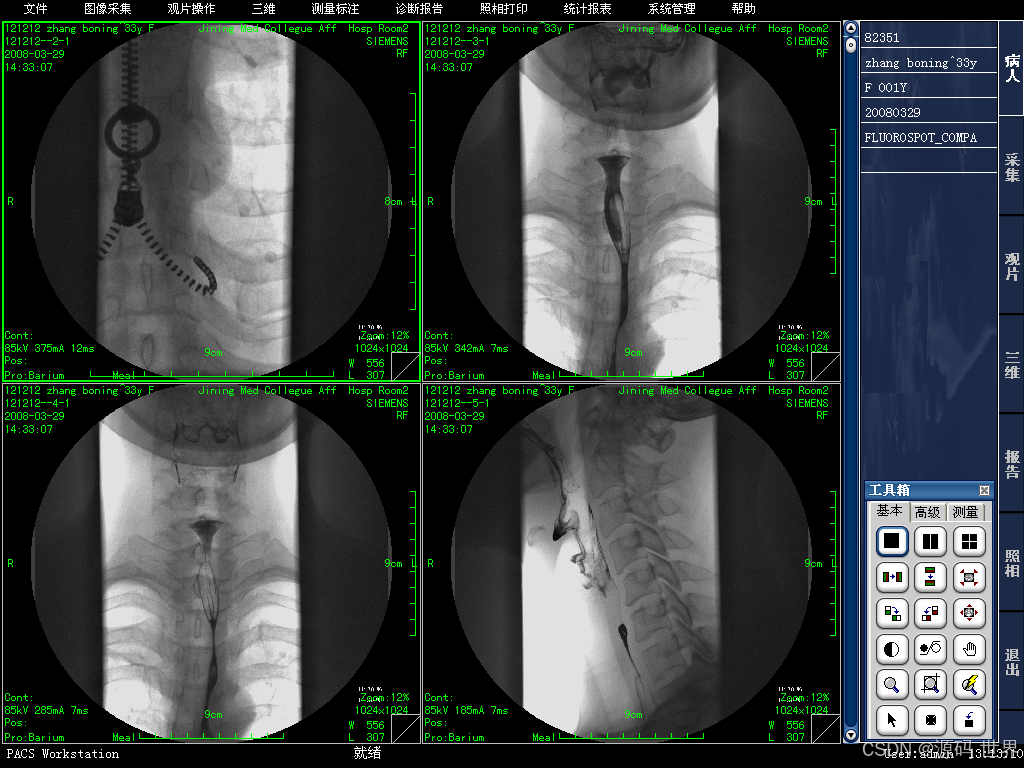

主要的任务就是把医院影像科日常产生的各种医学影像(包括核磁、CT、DR、超声、各种X光机等设备产生的图像)通过DICOM3、0国际标准接口(中国市场大多为模拟,DICOM,网络等接口)以数字化的方式海量保存起来,当需要的时候在一定的授权下能够很快的调回使用,同时增加一些辅助诊断管理功能。

1、影像设备:如X光机、CT、MRI、超声等医疗设备,用来产生医疗影像。

5、影像工作站:用于医生和专业技术人员查看、诊断、分析及操作影像的计算机和软件系统。